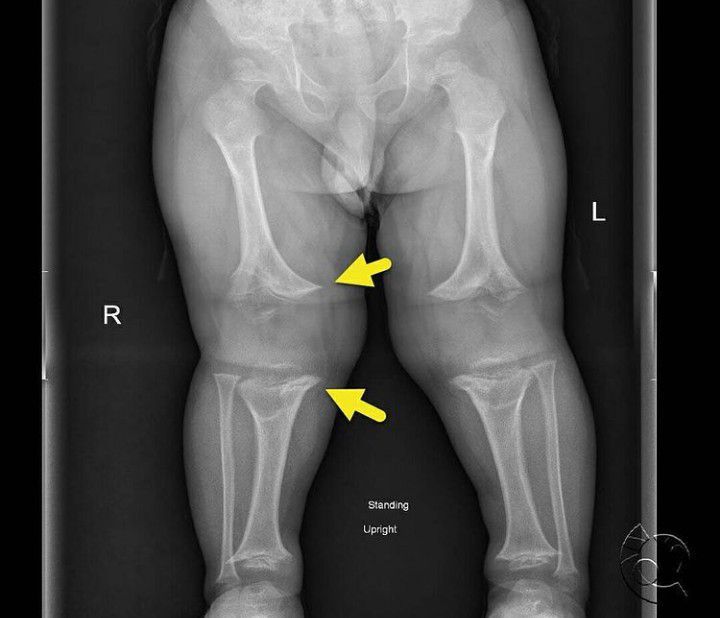

AP radiograph of the lower extremities (image 1) shows rhizomelic shortening and metaphyseal flaring (arrows). AP radiograph of the pelvis (image 2) shows a horizontal acetabular roof, small iliac wings, short sacroiliac notches, and a narrow pelvic inlet. The constellation of findings is characteristic of achondroplasia. Achondroplasia is the most common skeletal dysplasia. It typically occurs due to a sporadic mutation. However, it is in an autosomal dominant trait. The shortened pedicles seen on the spine can cause spinal stenosis.